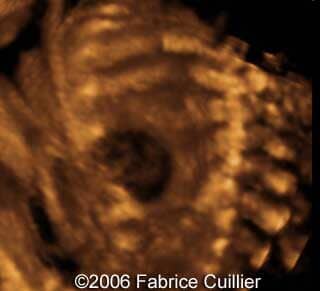

This is a 24- year-old-primigravida scanned at our unit at 21 weeks. During the first trimester, the nuchal translucency and the triple test were normal. At the end of the second trimester, the sonographer diagnosed a left polycystic kidney. The right kidney was normal with a normal corticomedular differentiation. The bladder was also normal. The patient refused additional investigations. We performed a scan at 21 weeks. The ultrasound findings were:

• an abnormal polycystic left kidney (34 X 17 mm) with an abnormal corticomedullar differentiation. This kidney was on the lumbar fossa.

At 24 and 26 weeks, the left kidney lesion had increased. At 34 and 37 weeks, the anomalies were the same. The baby was delivered vaginally (male, 3000 g). At day five, the kidney abnormalities were confirmed. Nevertheless the creatinine level was normal. One month later, a scan revealed a normal right kidney (50 mm) and a left kidney with cysts. The creatinine level was in the normal range. The child was operated (left nephrectomy). The diagnosis of multicystic kidney disease was confirmed.